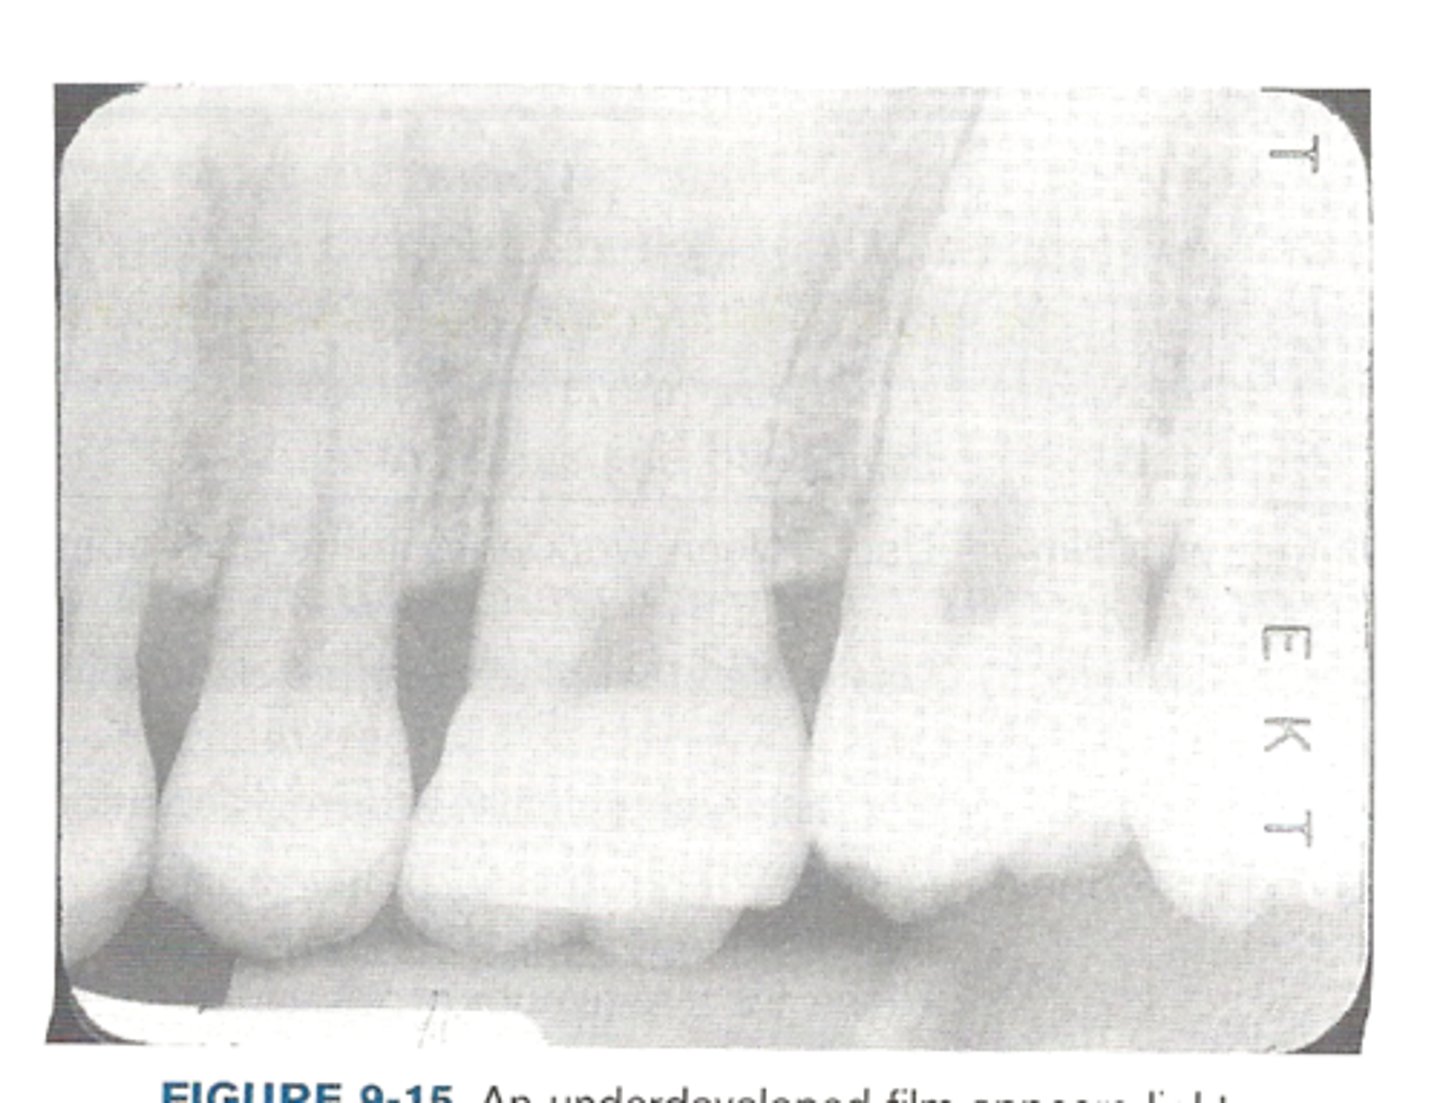

Underdevloped image

underdeveloped film